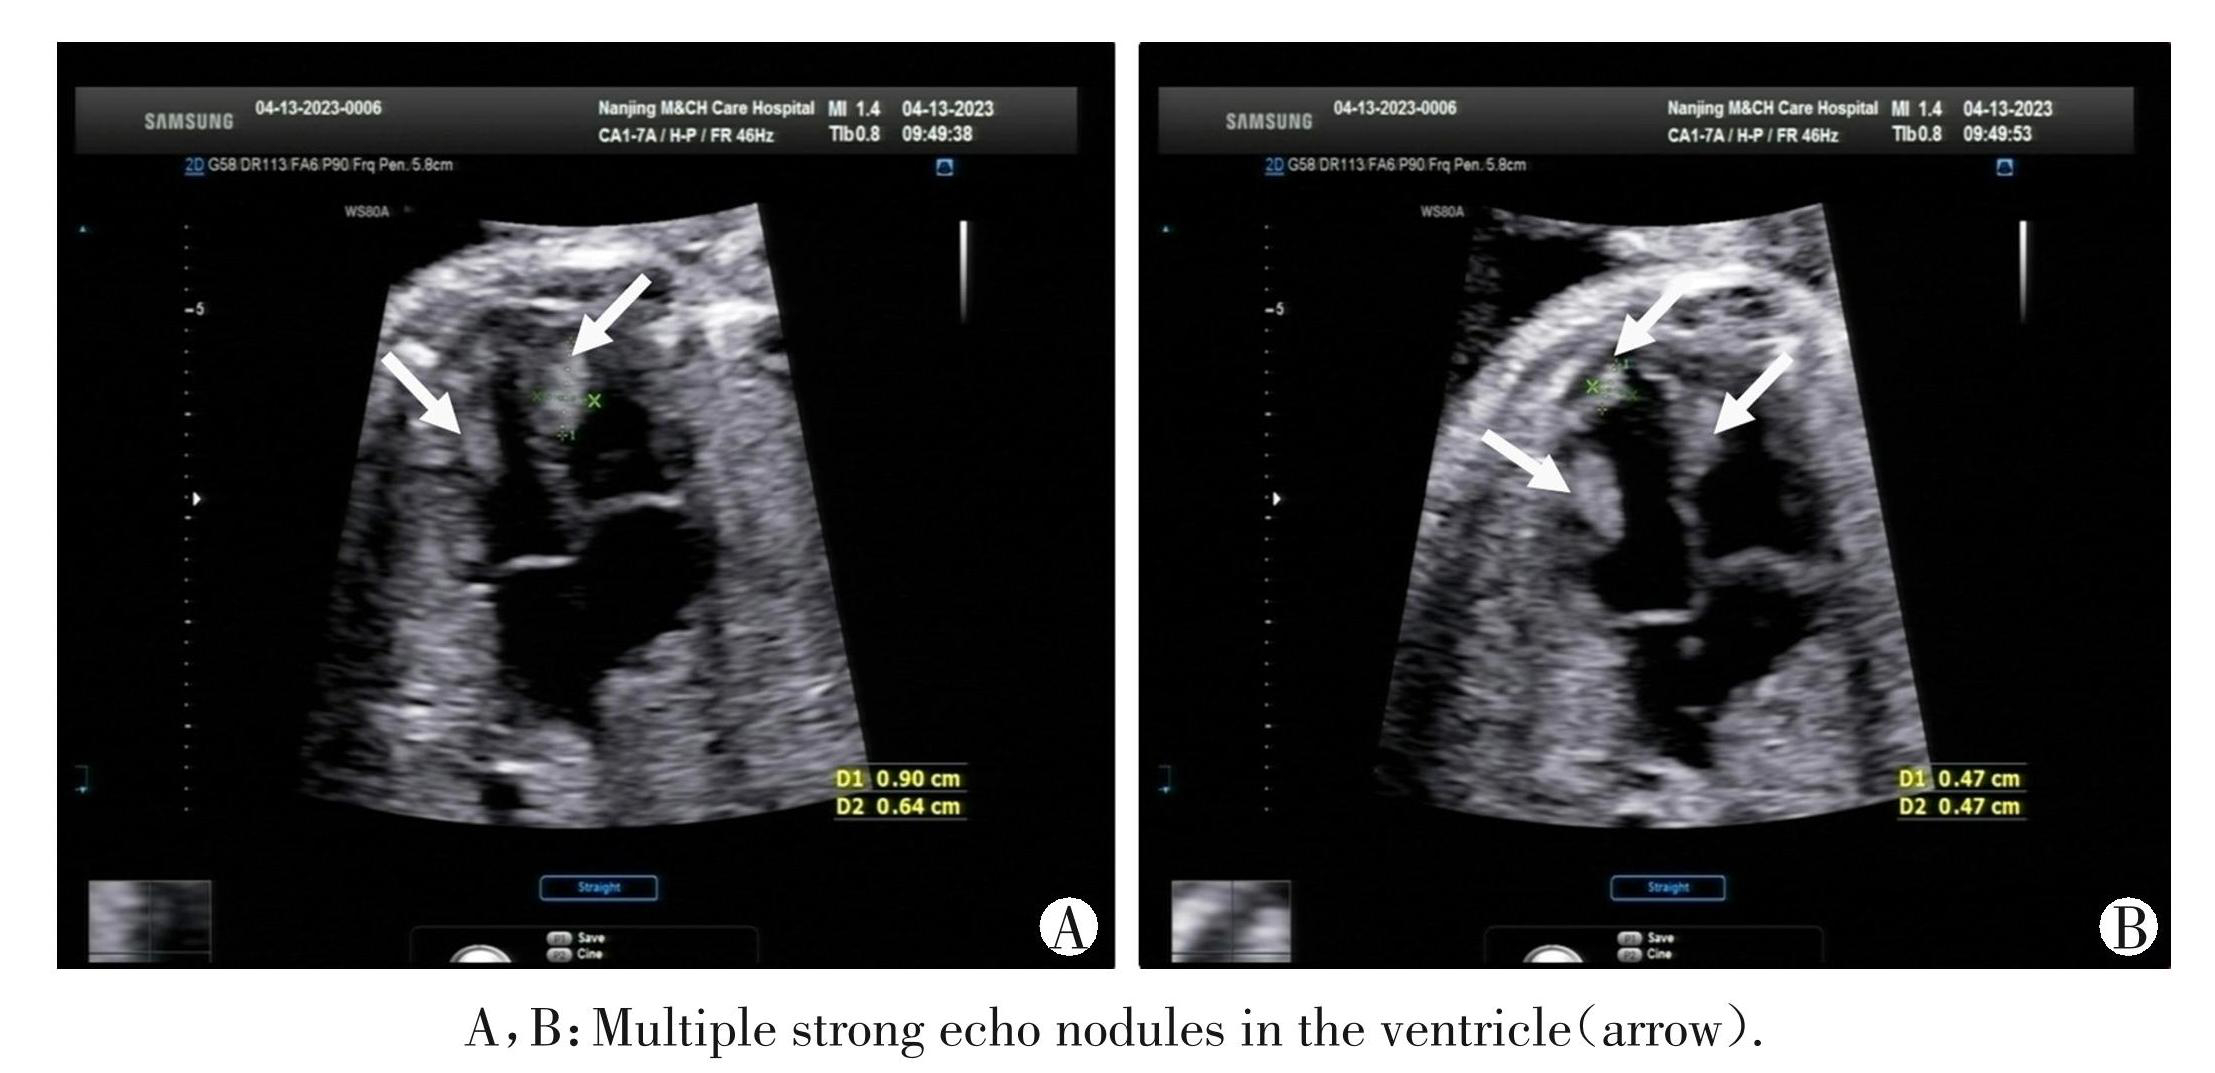

图2胎儿心脏多发横纹肌瘤(病例9)

Figure2Multiple rhabdomyomas of the fetal heart(case 9)

本研究结果表明胎儿心血管异常及骨骼系统异常在致病性变异中最多见,与既往研究结果基本一致[10-11]。其中病例 9 为心脏的多发性横纹肌瘤, WES 检测为 TSC2 基因杂合变异,与结节性硬化症 2 型有关。因此,WES能提高先心病胎儿致病性变异检出率,是CMA的有力补充。已有证据表明对骨骼发育异常胎儿行WES检测阳性率较高[12-13],涉及的基因包括FGFR3、COL1A1等,其中FGFR3突变与骨骼发育异常关系最密切。本研究中病例2为多发性骨骼发育异常,WES 检测为 FGFR3 基因杂合变异,与致死性骨发育不良、软骨发育不良等有关;病例10为股骨形态异常合并四肢长骨短,WES检测为 COLA1基因杂合变异,与成骨发育不全有关。因此 WES 可作为骨骼系统异常致病基因检测的重要方式,对明确其产前遗传学诊断有重要意义。